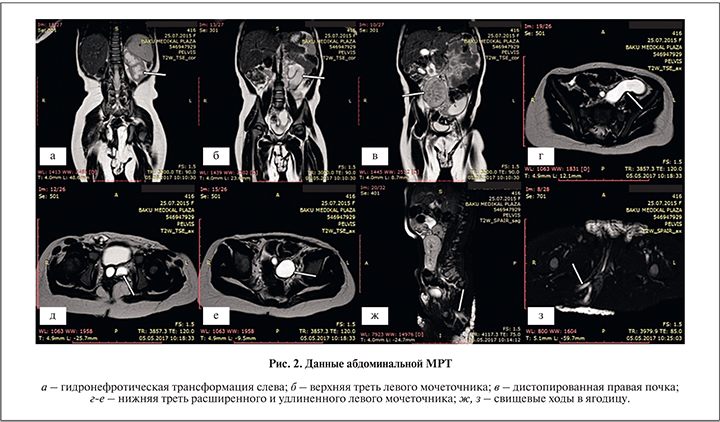

Показатели крови при поступлении: Нb – 126 г/л, эр. – 5,07×1012/л, л. – 9,92×109/л, СОЭ – 5 мм/ч, креатинин – 34 мкмоль/л. Общий анализ мочи без патологических изменений. При ультрасонографии определялась подвздошная дистопия правой почки, ее размер – 6,8×3,2 см, толщина паренхимы – 1,2 см, чашечно-лоханочная система (ЧЛС) не расширена, правый мочеточник в норме. Расположение левой почки нормальное, размер – 9,8×3,9 см, толщина паренхимы – 1 см, ЧЛС резко расширена, также отмечено значительное расширение левого мочеточника (уретерогидронефроз). Для уточнения диагноза ребенка проведена полная абдоминальная МРТ. Заключение: печень, желчный пузырь, поджелудочная железа, селезенка, надпочечники в норме. Правая почка нормальных размеров, подвздошно дистопирована и находится ближе к средней линии у подвздошно-крестцового сочленения. Толщина и сигнальная интенсивность ее паренхимы в норме. Справа ЧЛС и мочеточник не расширены. Правый мочеточник открывается в мочевой пузырь в нормальном месте. Левая почка в размерах увеличена, толщина паренхимы – 0,5 см. Слева резко расширены ЧЛС и мочеточник на всем протяжении. Наибольшая ширина левого мочеточника составила 22 мм, и он открывался в шейку мочевого пузыря у внутреннего отверстия уретры. Из его дистальной части прослежена короткая трубчатая структура, разветвленная на три ветви, открывающиеся в правую ягодичную область (рис. 2).

Учитывая отсутствие изменений при повторных анализах мочи, несмотря на периодическое повышение температуры тела, было заключено, что моча из левой почки в мочевой пузырь не поступает. Показатели УЗИ и МРТ убедительно свидетельствовали в пользу наличия обструкции в юкставезикальном отделе левого мочеточника, приведшей к образованию свищевых ходов. Все указанное было показанием к операции, в ходе которой при необходимости можно было провести дополнительные исследования для окончательного уточнения характера возникших изменений. В связи с этим эндоскопическое исследование (цистоскопия с попыткой катетеризации левого мочеточника) представлялось нецелесообразным.